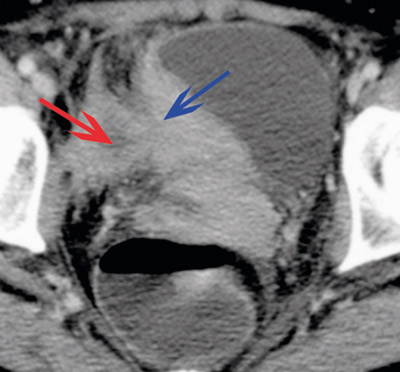

At A israelii gir en granulomatøs, suppurativ betennelse med fibrosedanning, gjenspeiles i bildediagnostiske undersøkelser. Et typisk funn er tykkveggede, cystiske tumorer med dårlig avgrensning til omkringliggende vev. De kan til forveksling likne maligne prosesser (fig 1, fig 2).

Ved computertomografisk (CT) undersøkelse dominerer som oftest solid vev, som har inhomogen kontrastoppladning i 80 % av tilfellene, med innslag av lavere tetthet eller tykkveggede cyster. Ved magnetisk resonanstomografi (MR) ses tilsvarende solid vev med innslag av flytende innhold. Signalet i de solide komponentene varierer med grad av fibrose, ved uttalt fibrose er det lavere T2-signal enn forventet ved maligne prosesser (som vanligvis inneholder mer væske) (26).

A israelii produserer proteolytiske enzymer som gir tendens til betydelig lokal infiltrasjon, som ved CT- og MR-undersøkelser ses som utvisking av normale barrierer og infiltrasjon i omliggende vev (27). Bakteriens størrelse forhindrer lymfespredning, og forstørrede lymfeknuter ses derfor sjelden (27).